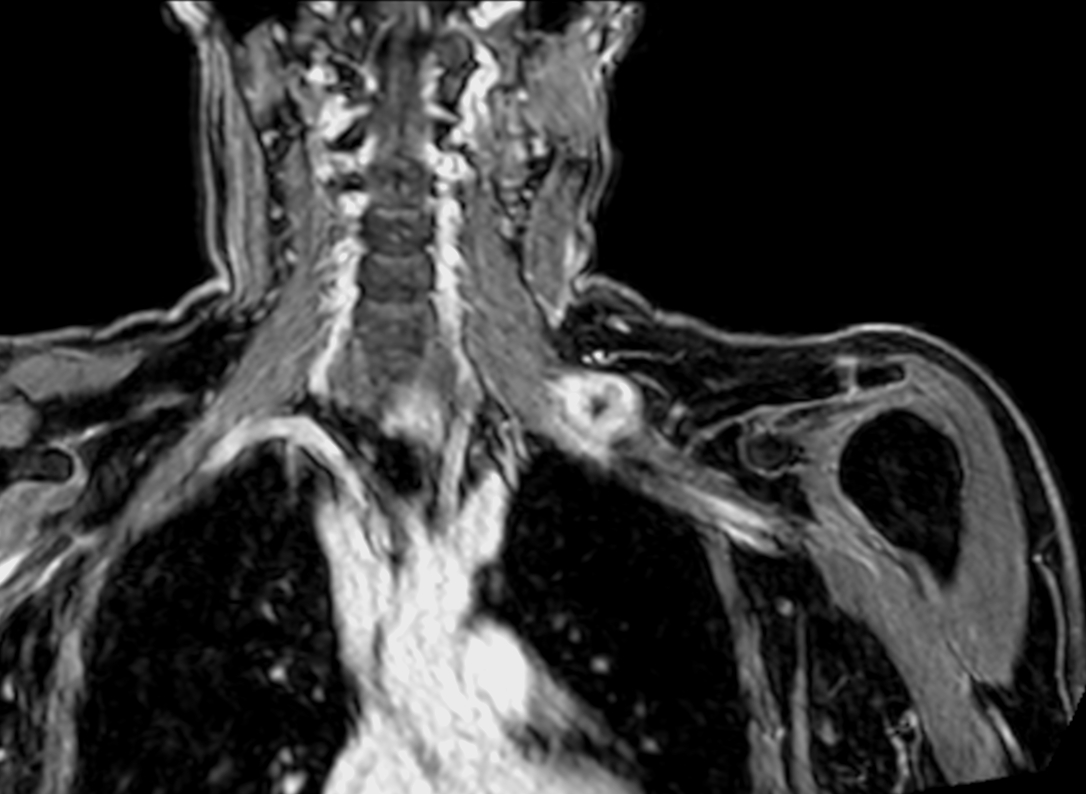

Brachial Plexus lesion

Coronal 3D STIR (MIP)